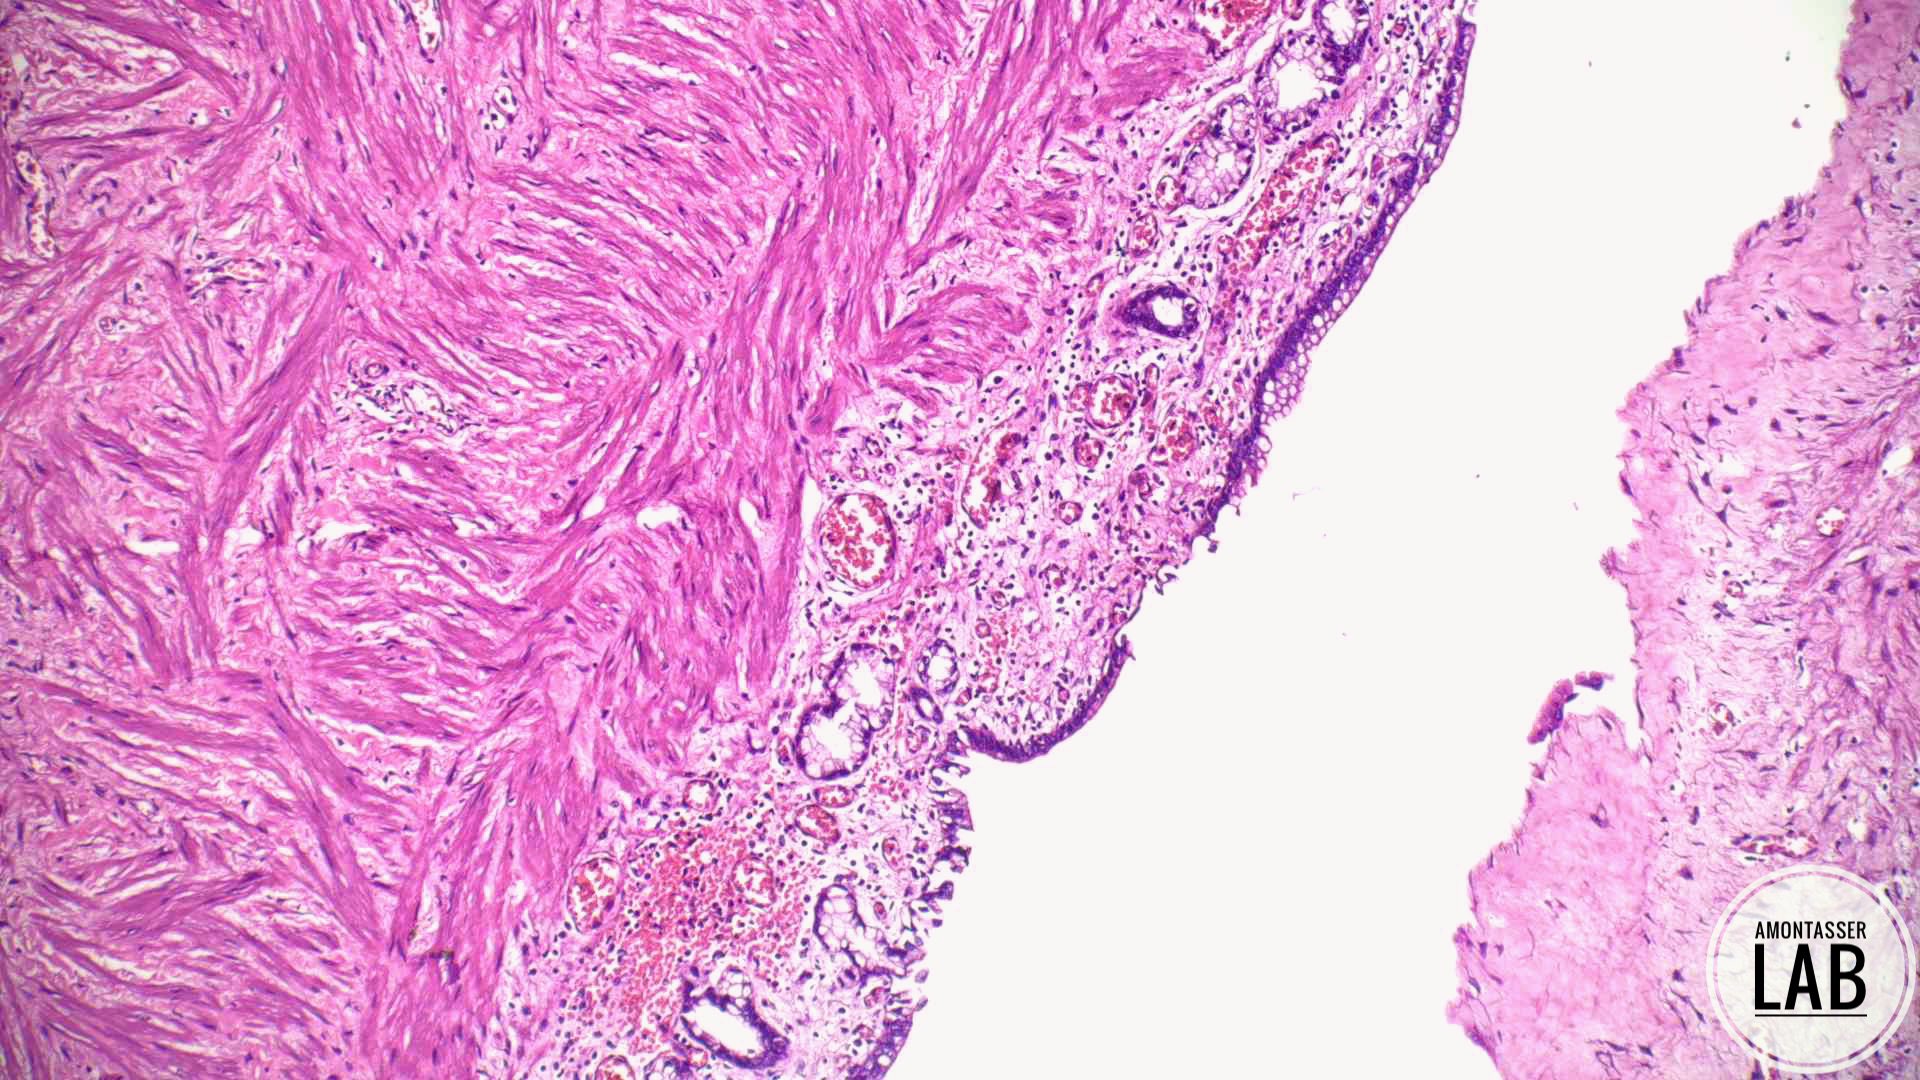

#PathX #PathTwitter #BreastPath #USCAP2026